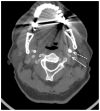

Eagle syndrome is a rare condition resulting from elongation of the temporal styloid process or calcification of its associated stylohyoid ligaments. Although usually presenting with pain or odynophagia, Eagle syndrome has been reported to cause a multitude of neurologic symptoms or vascular complications, some of which can be life-threatening. We present a case in which an endovascularly placed internal carotid artery stent in close proximity to a calcified stylohyoid ligament resulted in stent fracture with subsequent stent and vessel occlusion. We review and discuss the presentation, diagnosis, etiology, complications and treatment options of the syndrome.